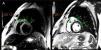

Three days after the first episode of chest pain, the patient had recurrence of the symptom and presented a fever (39ºC). On a physical exam, the patient had slight tachypnea, showing crackles in the lungs, blood pressure 112/72 mmHg, heart-rate 102 bpm and normal capillary filling. No murmur was auscultated in the chest. A pitting edema was noted in both legs. A second echocardiogram showed a LVEF decrease (LVEF 43%) and akinesis of basal portions of septal and inferior walls. Endovenous furosemide and low dose of nitroglycerin were started due to pulmonary congestion. The next day, CMR revealed the left ventricle with increased end-diastolic diameter and reduced contractile function with a LVEF of 42% (NR > 50%). The CMR depicted a marked hypokinesia in basal and mid portions of the anterior, anteroseptal and anterolateral walls and a large subepicardial area of edema and late-enhancement with non-ischemic pattern (Figures 1 and 2). The diagnosis of acute myocarditis was established. ATRA therapy was stopped and the antibiotic therapy scheme was amplified. The patient was already receiving intravenous corticosteroid dexamethasone 10mg daily since the start of the hospitalization . Bacteria and fungi blood cultures, polymerase chain reaction (PCR) for cytomegalovirus, parvovirus B19 and herpesvirus type 6 and serological tests for Epstein-Barr virus and toxoplasma gondii (Igm) were negatives. Coxsackie virus neutralizing antibodies showed small titers for B2, B4 and B5 subtypes, without a rise in titers in another sample that was collected a week ago. A possible association between ATRA therapy and myocarditis was hypothesized.